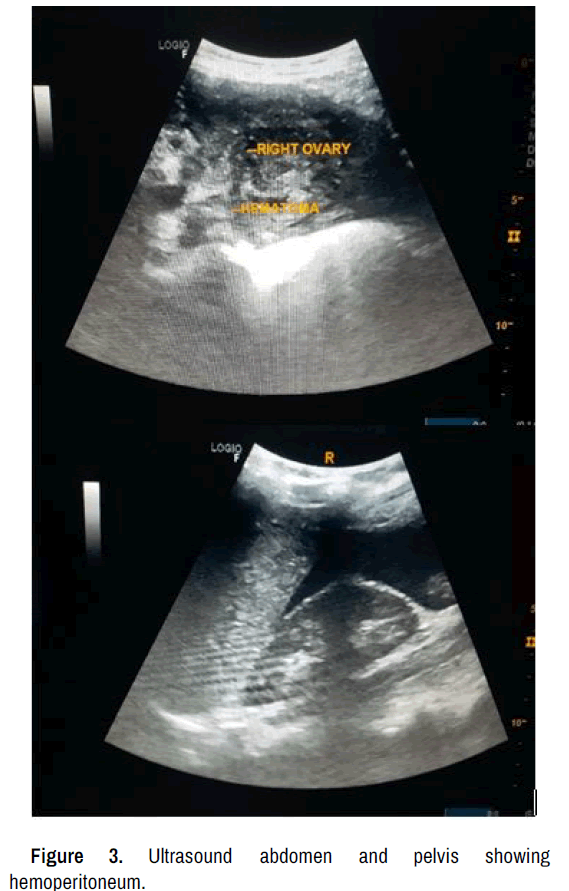

Preoperative laboratory investigation yielded a hemoglobin of 10.1 gm %, total leucocyte count of 16,970/ mm3 and serum beta HCG: 0.21 miu/ml. Diagnostic workup, including ultrasound abdomen with pelvis and CT screening confirmed the presence of moderate to large hemoperitoneum with suspected ruptured corpus luteal cyst (Figures 1-3).

Figure 1. CT-coronal view of abdomen and pelvis showing hemoperitoneum.

Postcoital hemoperitoneum is an uncommon condition resulting from rupture of an ovarian cyst, typically corpus luteal cyst. Its diagnosis is challenging due to nonspecific natre of symptoms. The presentation can mimic other causes of acute abdomen, such as ruptured ectopic, ovarian torsion. Prompt diagnosis and appropriate management is crucial to prevent severe morbidity and mortality. Clinical observations, laboratory findings and utilization of ultrasound images, CT films provide valuable insights into the diagnosis, surgical planning and assessment of treatment outcomes. Surgical intervention such as laparotomy plays a crucial role in managing post-coital hemoperitoneum when conservative management fails or in severe cases. Surgical approach aims to identify the source of bleeding and achieve hemostasis. Corpus luteum biopsy is performed to confirm diagnosis and assess for any associated pathologies.